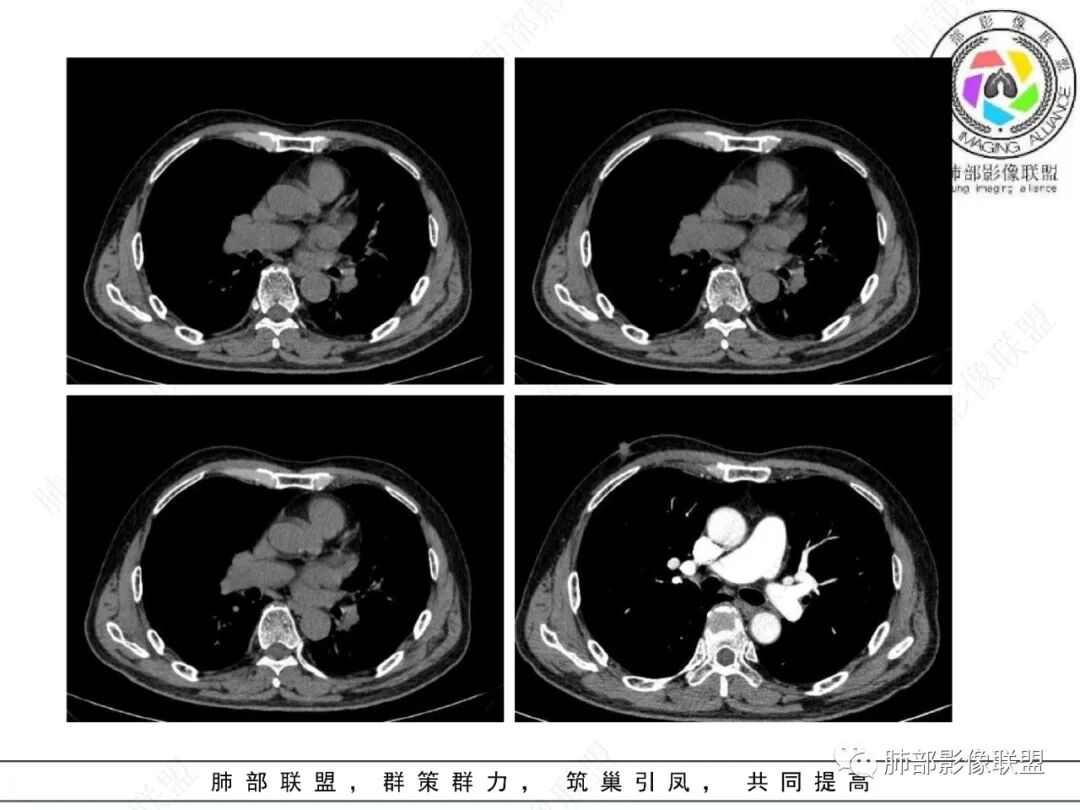

影像学表现:左肺下叶背段近叶间裂旁不规则实性密度结节影,图像未明确显示与支气管关系。边界清,整体膨隆感较明显,边缘显示分叶,偶见段毛刺,叶间胸膜“L”形牵拉凹陷,密度均匀,未见空洞或液化,也未见明显脂肪密度及钙化,轻到中度渐进性强化,未见明确蛇纹状血管应。左肺门可见多发小淋巴结影,纵隔内未见明显肿大淋巴结影。

未见明确卫星灶。